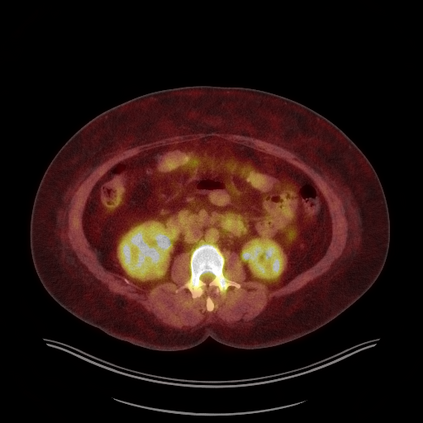

Medical images play a crucial role in assisting diagnosis, remote consultation, and academic research. However, during the transmission and sharing process, they face serious risks of copyright ownership and content tampering. Therefore, protecting medical images is of great importance. As an effective means of image copyright protection, zero-watermarking technology focuses on constructing watermarks without modifying the original carrier by extracting its stable features, which provides an ideal approach for protecting medical images. This paper aims to propose a fragile zero-watermarking model based on dual quaternion matrix decomposition, which utilizes the operational relationship between the standard part and the dual part of dual quaternions to correlate the original carrier image with the watermark image, and generates zero-watermarking information based on the characteristics of dual quaternion matrix decomposition, ultimately achieving copyright protection and content tampering detection for medical images.